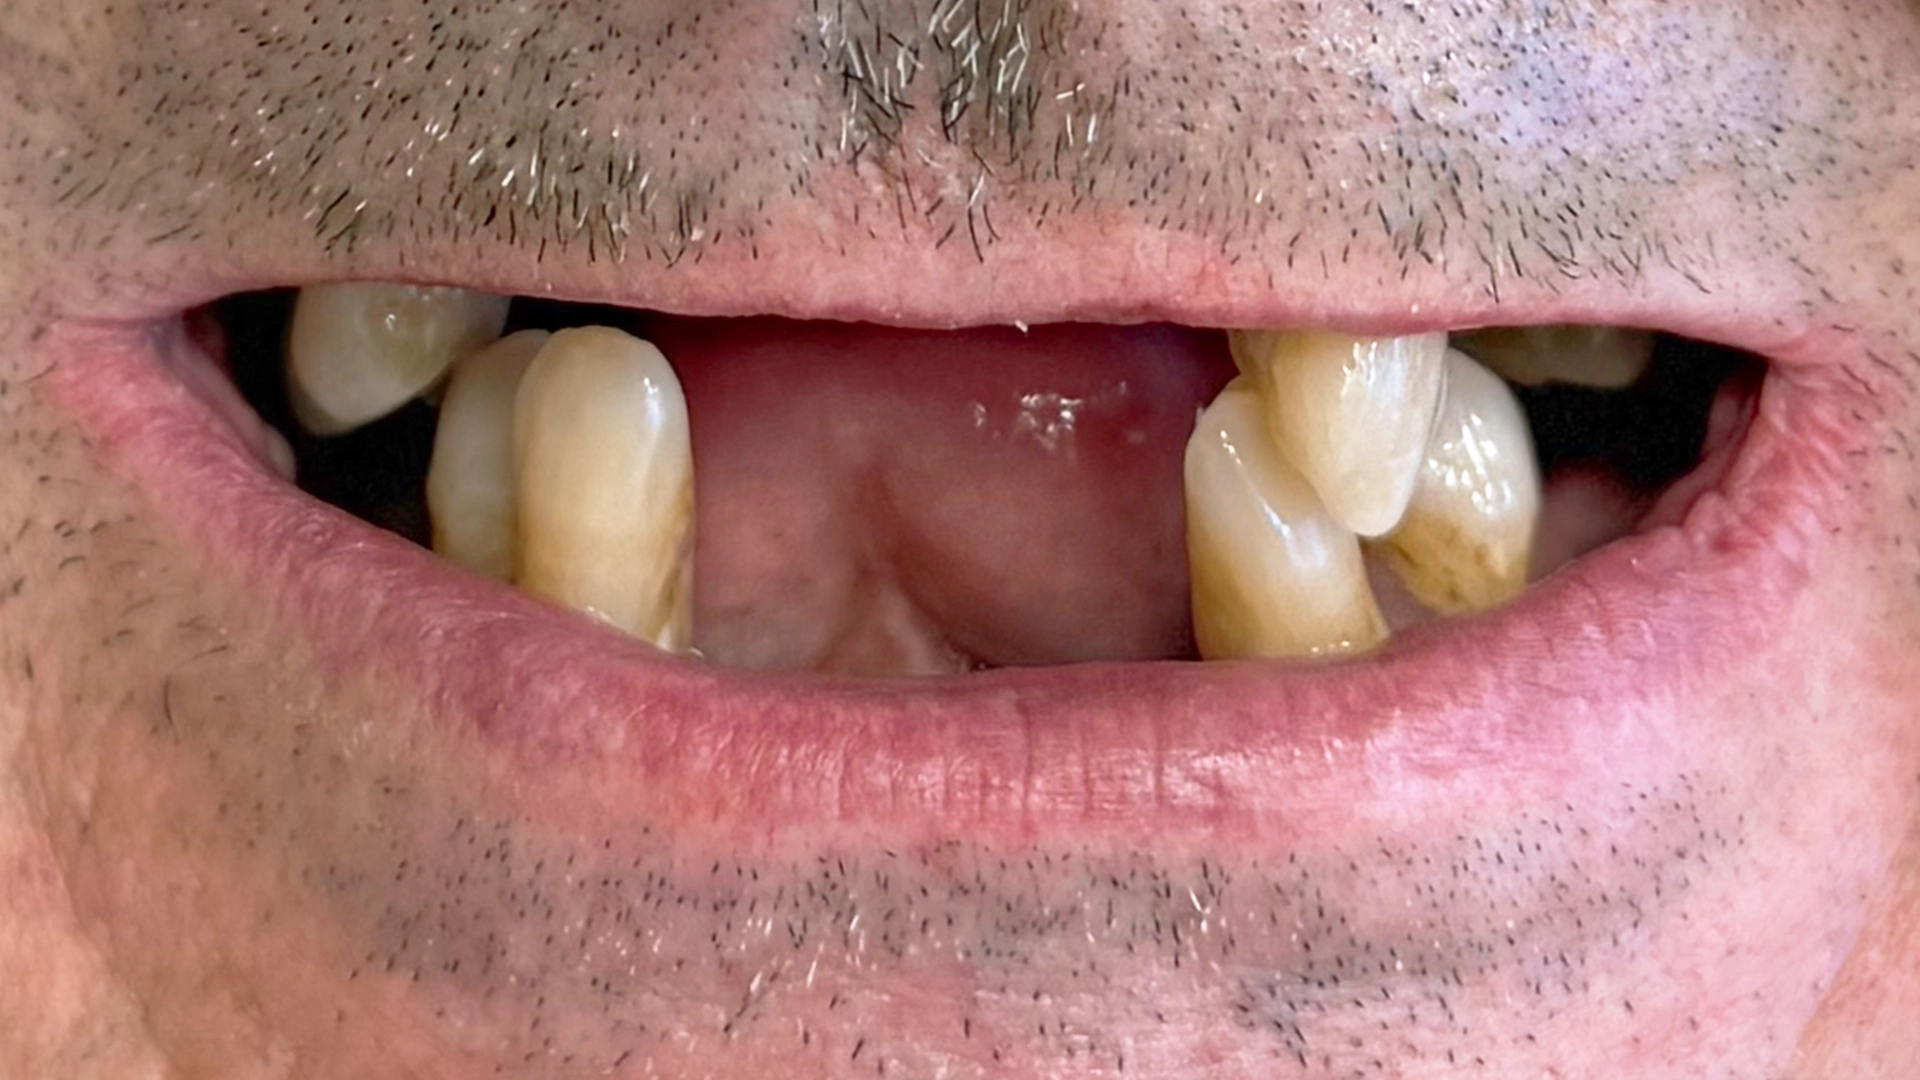

Before dental implant – missing or damaged teeth

Before After

Before dental implant – teeth needing implant evaluation